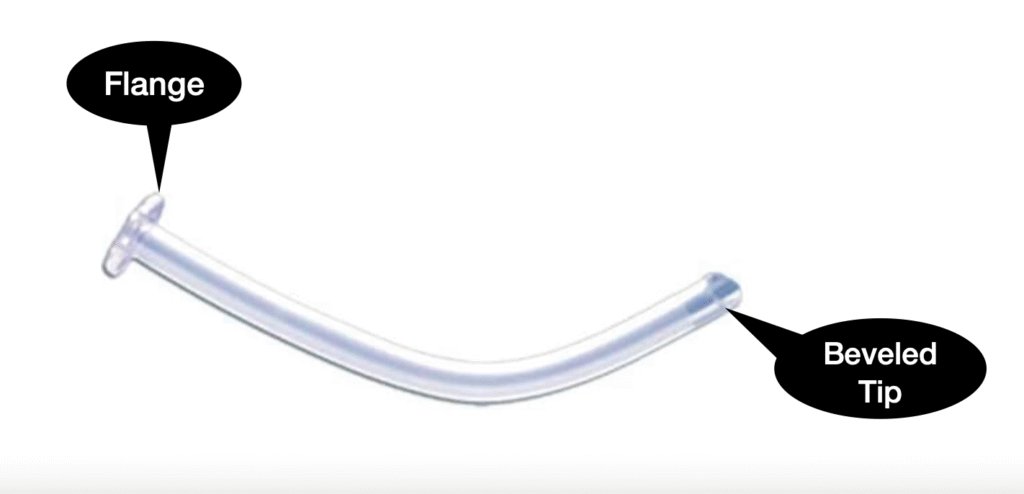

Nasopharyngeal Airway-

| Aspect | Nasopharyngeal Airway (NPA) in PALS |

|---|---|

| Purpose | Maintain airway patency for unconscious, conscious, or semi unconscious patients |

| Indications | Unconscious, conscious, or semi unconscious patients requiring airway support |

| Insertion Technique | 1. Measure from the corner of the nose to the tragus of the ear |

| 2. Choose size based upon the diameter of the nostril (a 12F or 3mm will generally fit a full term infant) | |

| 3. Gently insert through one nostril, directing posteriorly | |

| 4. Secure in place and monitor for discomfort or complications | |

| A shortened E.T. tube may be used | |

| Removal | Remove upon regaining consciousness and ability to maintain a clear airway independently |